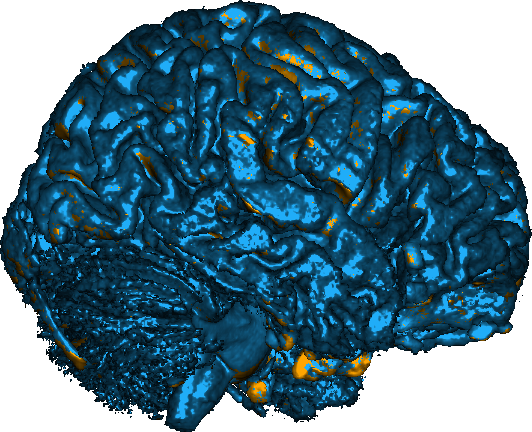

To motivate our work, consider the example in Fig. 1, in which we performed a 3D registration of two MRI brain scans from the OASIS [7] dataset using the popular Stationary Velocity Field (SVF) approach [8, 9, 10] and our proposed method (denoted ). In the first example, the sought deformation is comparably small before the registration process, and both approaches perform equally well. In the second example, the deformation includes a larger rotational component. When looking at the deformed images only, the SVF approach appears to generate an alignment that is clearly worse, but not catastrophically so. This is deceptive: inspecting the generated deformation fields (Fig. 2), it becomes clear that the SVF approach generates a deformation that – while it maps corresponding intensity values reasonably well between the images – is far from the ground truth.

The findings on these (synthetic) examples are compatible with our perception of the existing literature: In general, we found that SVF-based approaches mostly seem to be applied to pre-aligned images, and/or that the judgement of their accuracy is solely based on the similarity of the images after registration or on related proxies, such as the overlap of known segmented regions, that do not necessarily imply sensible deformation fields.

This behavior is clearly visible in Fig. 1 and Fig. 2 shown in the introduction, in which the resultant images as well as an exemplary slice of the deformation field are depicted under small and large deformations. It illustrates how the matrix group approach is able to capture even large rotational deformations, whereas the use of an SVF tends to align the intensity values by local deformations instead of a global rotation, resulting in the large RMSE observed in Fig. 12.